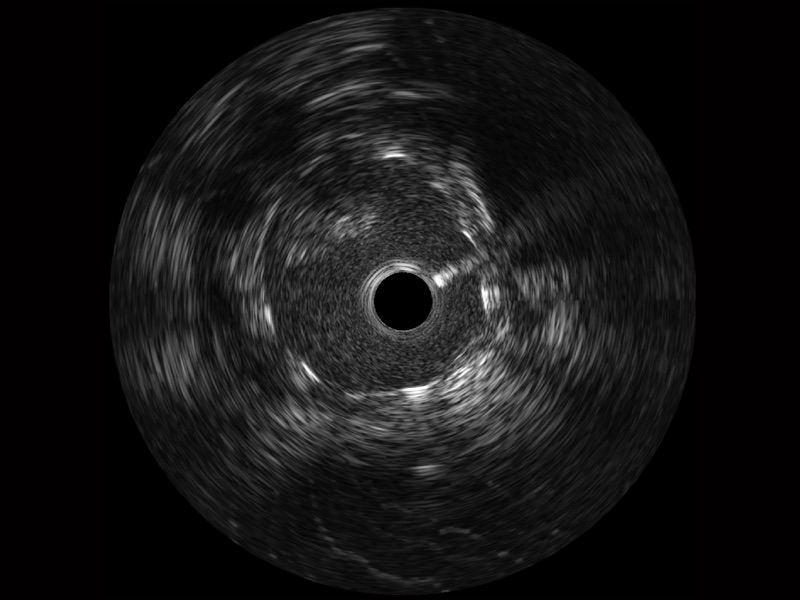

传统IVUS图像

对比传统IVUS导管成像,MILE米乐集团官网宽频IVUS图像的近场支架梁显影更细腻,远场中膜外血管仍清晰可辨,兼顾远中近,兼顾分辨力与穿透深度